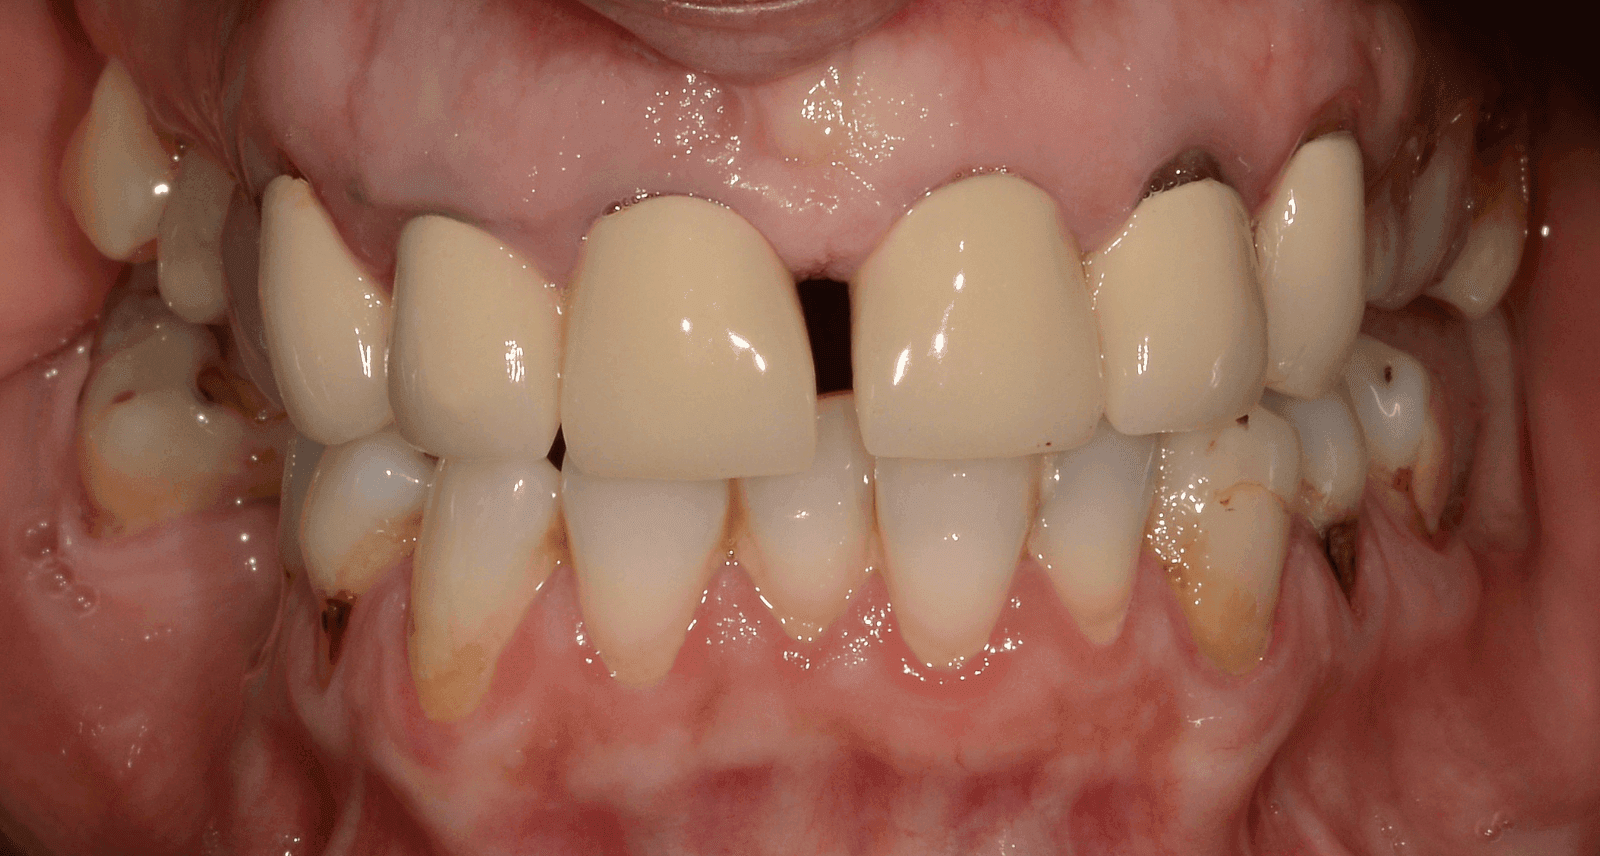

Pacijentkinja je želela da reši problem nedostajućih zuba i unapredi izgled svog osmeha. Zajedno smo prošli kroz proces koji je uključivao detaljnu analizu, ugradnju implantata i izradu krunica. Rezultat? Osmeh koji je oduševio i nju i nas! Evo kako je sve to izgledalo, korak po korak.

Prvo smo uradili snimak zuba da vidimo kakvo je stanje Gordaninih zuba i korenova. Nakon razgovora sa pacijentkinjom došli smo do zaključka da bi nedostajuće zube želela da nadoknadi implantatima. Zatim smo napravili 3D snimak kako bismo proverili da li ima dovoljno kosti za ugradnju implantata.